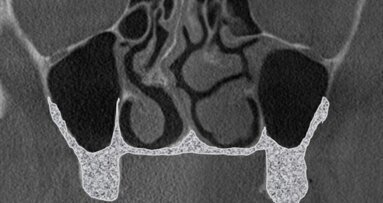

W 2015 r. polski autor Radosław Jadach przedstawił pracę oryginalną, w której opisuje zabieg podniesienia dna zatoki szczękowej z dostępu od strony podniebiennej jako metody alternatywnej.7 Zabieg wykonano u 39 pacjentów. Autor opisuje również własną klasyfikację, na podstawie której łatwiejsze będzie podjęcie decyzji odnośnie tego która z metod podniesienia dna zatoki szczękowej będzie bardziej odpowiednia dla danego przypadku klinicznego. Klasyfikację tę autor stworzył na podstawie analizy 200 badań tomografii komputerowej wiązką stożkową (CBCT). Klasyfikacja przedstawia podział ze względu na grubość blaszki kostnej od strony przedsionkowej i podniebiennej w sposób następujący:

Daisuke i wsp. opisali przypadek, gdzie zastosowanie dostępu od strony podniebienia było uzasadnione i stanowiło jedyną możliwość, aby pacjent mógł w przyszłości mieć wykonaną odbudowę implantoprotetyczną.8 Ze względu na niewystarczający wymiar pionowy kości nie można było pogrążyć implantów w pożądanych pozycjach, zatem zdecydowano się wykonać podniesienie dna zatoki szczękowej z dostępu klasycznego od przedsionka. Podczas zabiegu doszło do perforacji błony Schneidera o długości ok. 10 mm. Perforację zaopatrzono oraz dokończony procedurę augmentacji materiałem kościozastępczym. Po wykonaniu kontrolnego zdjęcia CBCT po upływie 5 miesięcy stwierdzono niewystarczającą formację tkanki kostnej od strony podniebienia oraz w części dystalnej. Ze względu na to, że od strony przedsionka doszło do prawidłowej osteogenezy, zdecydowano o wykonaniu zabiegu augmentacji od strony podniebienia. Następnie wprowadzono 2 implanty podczas tej samej wizyty, co wskazuje na odmienne postępowanie niż zalecane przez Jadacha.